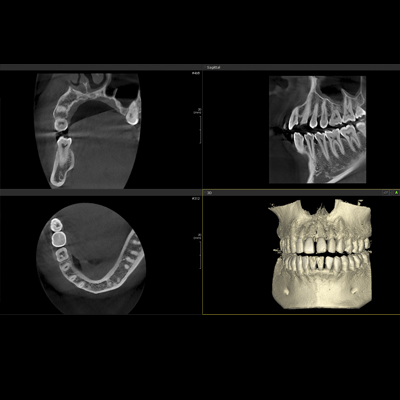

PAPAYA 3D

Diaqnostik kompyuterli erqonomik rentgen sistemi

-3D CT, Panorama

-Çoxsaylı -FOV seçimi (4×5, 14×14)

-Açıq yerləşdirmə (üzbə - üz)

-Çoxsaylı Fokuslanma

-70um görüntülü ENDO rejim